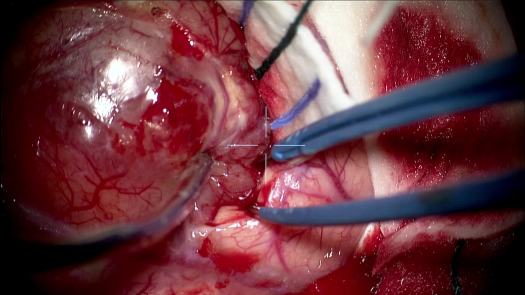

Resezione microchirurgica di tumore cerebrale (glioma alto grado cortico-sottocorticale) frontale dx